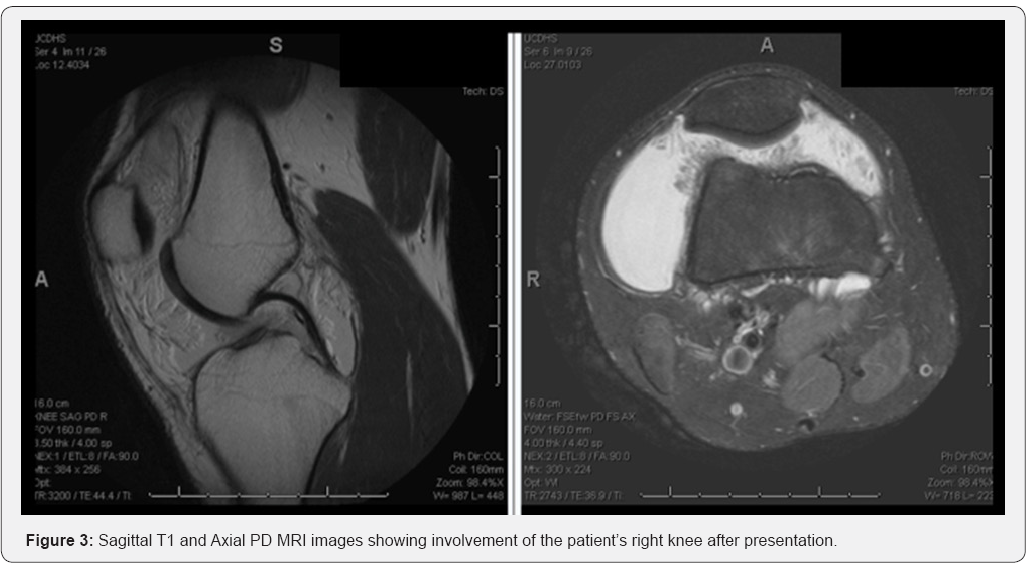

In addition to cartilaginous injury to the medial facet of the patella from his dislocations, the new MRI of his left knee revealed diffuse fatty hypertrophy of his synovium, with villous and arboreal architecture throughout the knee joint (Figure 2). An MRI was ordered for his contralateral knee given its non-painful large effusion showing similar findings of the synovium (Figure 3). Due to the severity of his recurrent effusions and difficulty performing his job duties in the automotive industry, the patient elected to have bilateral diagnostic arthroscopies with synovial biopsies and complete arthroscopic synovectomies.